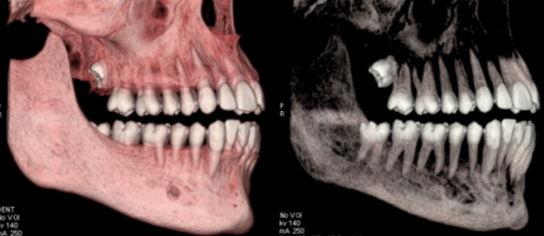

Les nouvelles générations de scanner permettent de faire une acquisition d’un volume global d’une partie du corps et de travailler à l’intérieur de ce volume en isolant une structure anatomique donnée et de l’explorer dans tous les plans de l’espace.

Grace à la technique de seuillage il est possible de dissocier progressivement les dents des structures osseuses environnantes dans le volume donné.